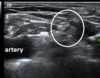

what are these circled guys? (this is a right sided supraclavicular approach to brachial plexus)

brachial plexus divisions | (lateral to artery)